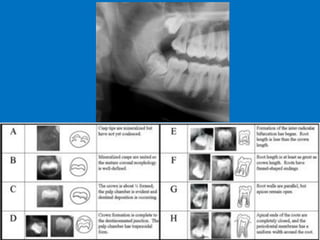

Age Estimation

1. The Universal System ( > reliable for children and

adolescents) analysis of dental development & X-ray.

2. Gustafson

Looking for six signs of wear

3. Lamendin / Johansen methods

Transparency of radicular dentin (older the person >

translucent the root dentine) and secondary dentin

deposition.

Age Estimation • Youcan tell age solely by teeth analysis: • Methods: 1. Require the extraction of teeth and histopathological examination, and 2. Require radiographs. D. Caroline Mohamed 47

• 48.

Age Estimation 1. TheUniversal System ( > reliable for children and adolescents) analysis of dental development & X-ray. 2. Gustafson Looking for six signs of wear 3. Lamendin / Johansen methods Transparency of radicular dentin (older the person > translucent the root dentine) and secondary dentin deposition. D. Caroline Mohamed 48